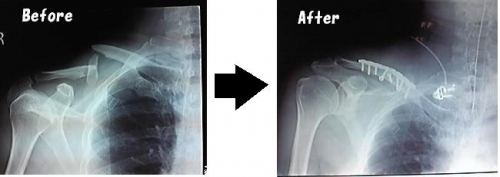

先日、バイクで転倒してしまい「右鎖骨粉砕骨折」で入院中に「C1000 1日分のビタミン 190g 6本」当選しました入院、手術、発熱で痛い苦しい中のど越しさわやかで、更に入院中不足になるビタミンが補給され回復に向かっていますおいしく、さわやか、入院中のビタミン補給に一石三鳥とてもありがたい入院のお見舞いにもこれなら大丈夫喜ばれること間違いなし 続きを見る ['close']